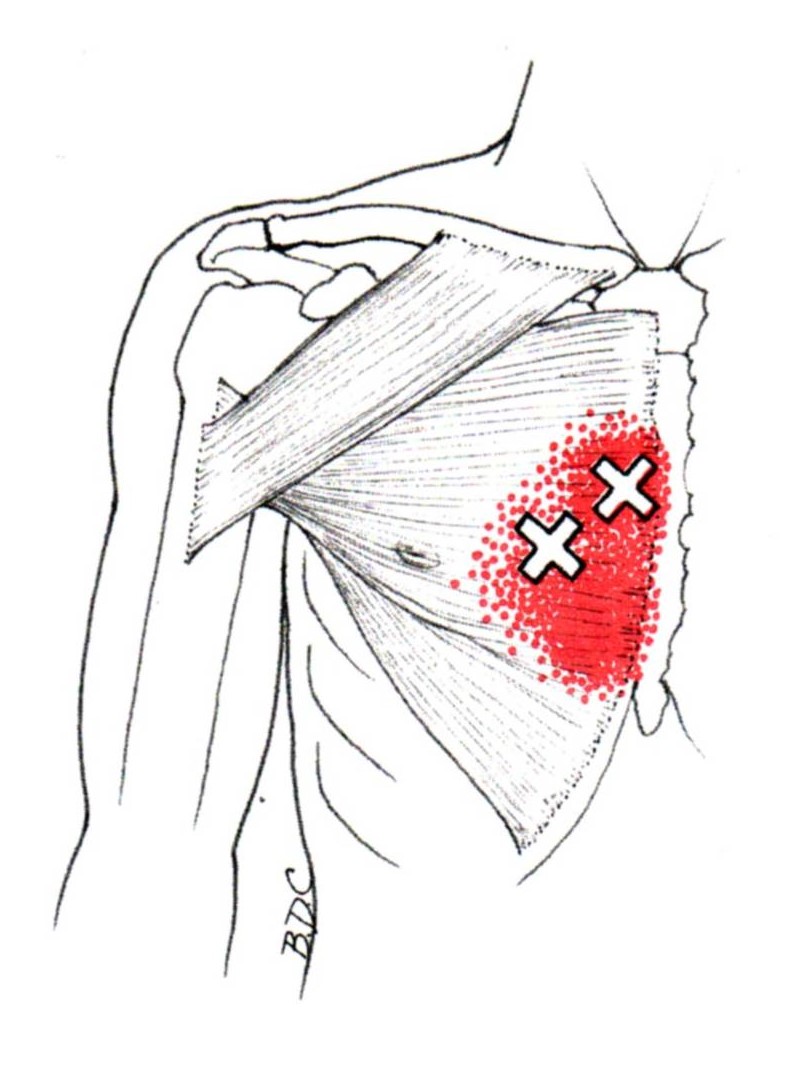

육.트리거 포인트

통증 유발점은 통증과 불편함을 유발하는 근육 긴장 또는 과사용 영역입니다. 대흉근도 예외는 아니며 신체의 다른 부분에 통증을 유발하는 통증유발점을 만들 수 있습니다.

대흉근의 통증유발점은 일반적으로 흉골에 부착되는 근육의 흉골 부분에 있습니다. 이러한 통증유발점은 가슴, 어깨, 팔에 통증과 불편함을 유발할 수 있습니다.

통증 유발점이 대흉근에 있을 때 신체의 다른 곳에서 느낄 수 있는 연관통을 유발합니다. 통증은 어깨, 팔 또는 손으로 퍼질 수 있습니다.

대흉근의 통증유발점은 과도한 사용, 부상, 잘못된 자세 등 다양한 요인으로 인해 발생할 수 있습니다. 통증유발점 마사지, 스트레칭, 근력운동 등으로 치료할 수 있습니다. 더 이상의 통증과 불편함을 유발하지 않도록 대흉근 통증유발점에 대한 치료를 찾는 것이 중요합니다.